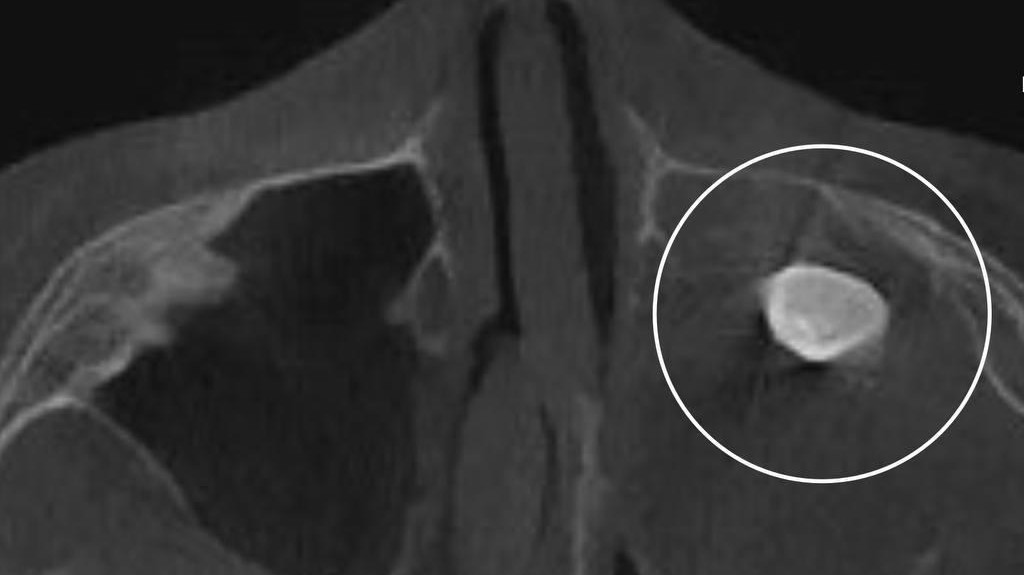

В Детскую городскую больницу им. Н.Ф. Филатова обратился за консультацией 15-летний мальчик с жалобами на асимметрию лица и заложенность носа. Помощь подростку понадобилась в связи с тем, что специалисты частной клиники нашли у него в гайморовой пазухе сформированный зуб, сообщила пресс-служба Департамента здравоохранения Москвы.

Новообразование отправили на исследование и выяснили, что это тератома. Хирург-оториноларинголог Вугар Достиев обратил внимание, что эти эмбрионально-клеточные новообразования очень редко располагаются в зоне лица, чаще всего в крестцовой области. По его словам, КТ и рентген не показали тератому, поскольку фактически она занимала «всю левую полость носа». Хирург оценил проведение редкой операции как успешное. Тератома оказалась доброкачественной. После восстановления функций подростка выписали с хорошим самочувствием, асимметрия его лица и заложенность носа полностью исчезли, уточнили в Депздраве.